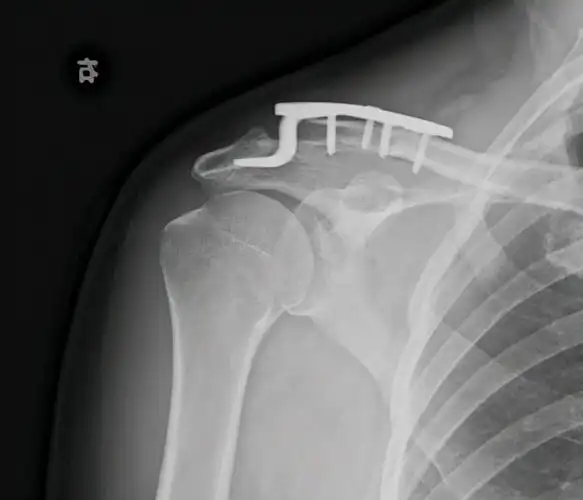

男子车祸致肩锁关节脱位微创手术复位快速康复